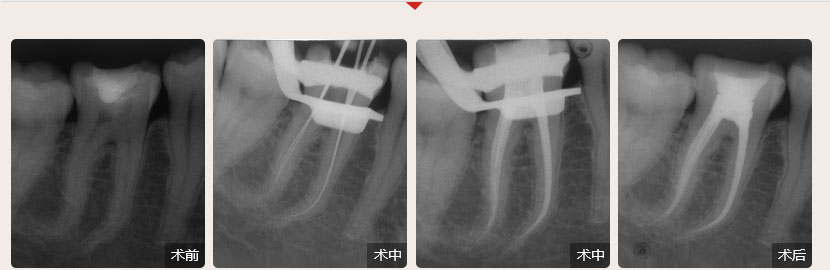

德倫口腔醫(yī)生全國(guó)根管治療技術(shù)競(jìng)賽獲獎(jiǎng)案例展示

根管治療過(guò)程